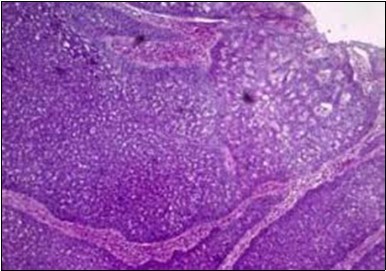

Granular arrangement of malignant cells and intercellular bridges are conspicuous with the demonstration of nuclear atypia, pleomorphism, prominent mitosis and tumour necrosis. A peripheral palisade is discernible within the cellular aggregates. Mitotic figures are common and can be quantified as up to 12 mitosis/ high power field. Tumour differentiation can prominently be of the ductal category with the demonstration of intra-cytoplasmic lumina. Comedo type tumour necrosis is evident along with foci of squamous differentiation The neoplasm is reactive to periodic acid Schiff ‘s (PAS) stain. (Figure 1, Figure 2, Figure 3, Figure 4, Figure 5, Figure 6, Figure 7, Figure 8, Figure 9, Figure 10, Figure 11, Figure 12, Figure 13.

Figure 1.Solid aggregates of tumour cells and duct structures in eccrine porocarcinoma (14).